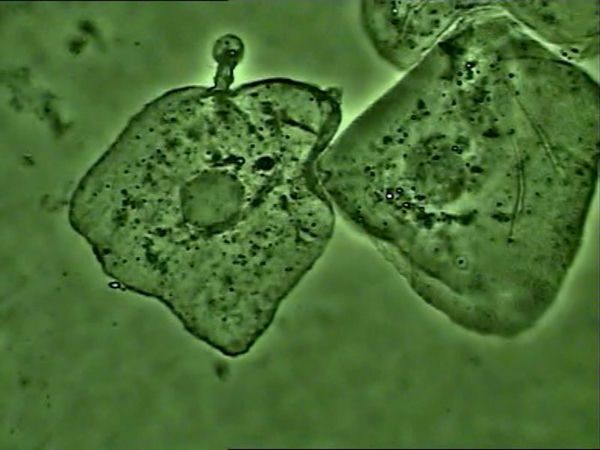

·顯微鏡下的肺炎支原體

支原體感染的細(xì)胞

支原體主要黏附在細(xì)胞膜上生存,使用光學(xué)顯微鏡高倍相襯觀察,如果看到細(xì)胞核周?chē)罅快o止或布朗運(yùn)動(dòng)的小黑點(diǎn),可以推斷大概率為支原體。